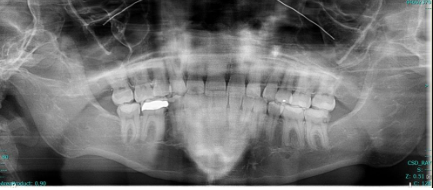

CT Maxillofacial soft tissue views of patient in Case 2